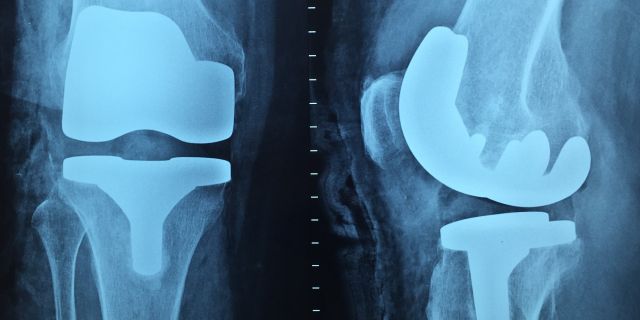

Wie unterscheidet sich die Versorgung von gesetzlich Krankenversicherten und Selbstzahlern („Privatversicherten“)? Der NDR hat gestern eine 45minütige Sendung ausgestrahlt, in der dieser Frage anhand zweier Fallbeispiele zur Knie-Endoprothese nachgegangen wurde. Im Ergebnis sind die Unterschiede in der Medizinischen Versorgung nicht so groß wie immer vermutet, in der Zuwendung aber sehr wohl; die Sendung erscheint als ein gelungener Beitrag zur Versachlichung einer politischen Diskussion.